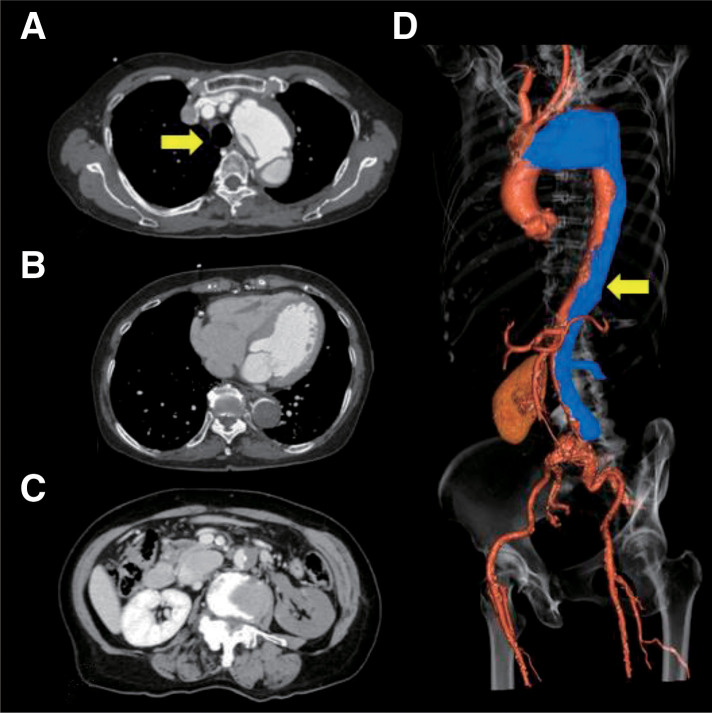

An 84-year-old woman with an acute type B aortic dissection (ATBAD), an entry tear in a distal arch aneurysm, and lower-body malperfusion underwent a hybrid approach combining total arch replacement with an elephant trunk (TAR+ET), thoracic endovascular aortic repair (TEVAR), and left renal artery stenting. This strategy avoided direct resection of the aneurysm or primary entry, yet stabilized hemodynamics and restored organ perfusion. Postoperative CT was favorable, and the patient was discharged without complications. In this elderly case of complicated ATBAD involving a distal aortic arch aneurysm, we performed TAR+ET, TEVAR, and renal artery stenting, and achieved a favorable outcome.

Abstract Image